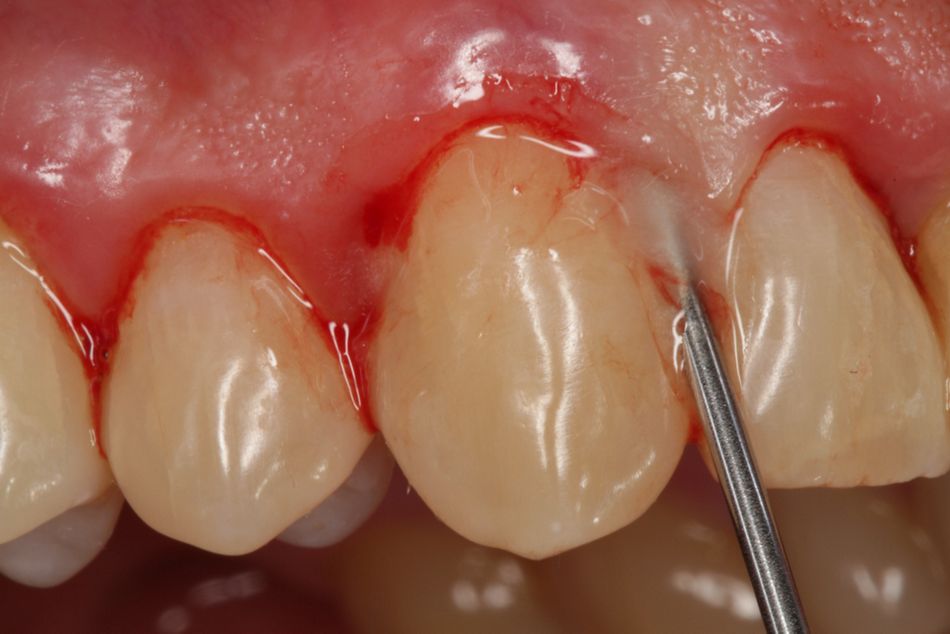

Ultimately, it is just another “surgical” approach. I don’t use a scalpel, but rather a periosteal elevator or a papilla elevator and I widen the gingiva. Once I have good access, I work with curved Slimline ultrasound attachments. They are not sharp and the tip is cooled, i.e. I can also work subgingivally and do not risk damage to tissue posed by thermal trauma. I have coined the term “tension flap” to describe the procedure.

Bröseler: “I find these fine cannulae very practical in reaching the bony base of the defect.”

Fig. 9: Straumann® Emdogain® FL for minimally invasive flapless surgery. The fine cannula makes it easier to apply the gel.